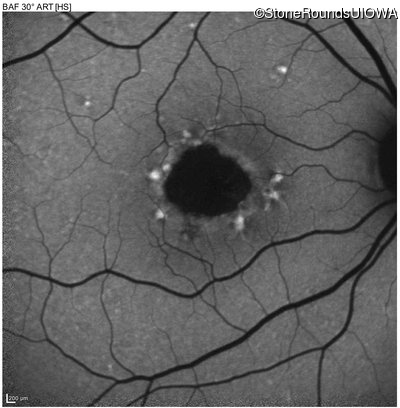

Infrared Fundus Photograph - Left - 20/160 -1 sc

Exemplar